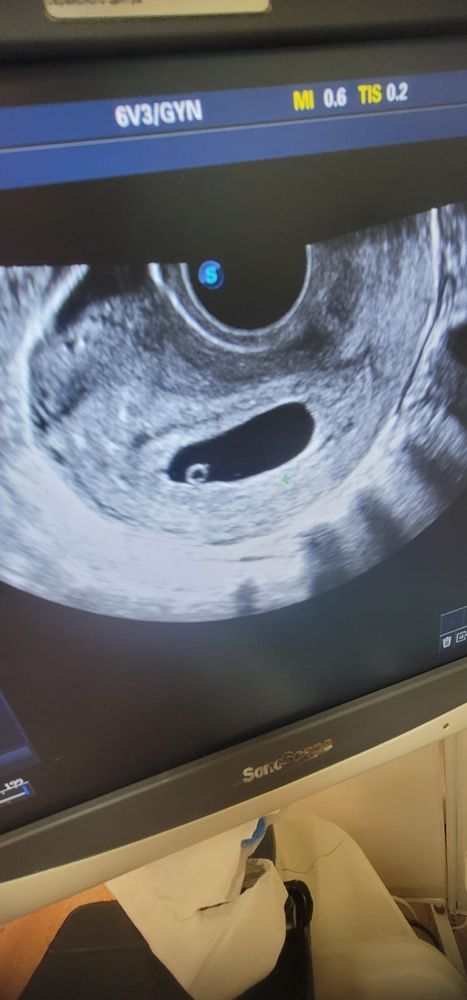

Девочки, подскажите, врач говорит, что задержка развития беременности, подозрение на неразвивающуюся, живот не болит, выделений нет, на первом узи 26.09 обнаружили плодное яйцо диаметром 18мм, ктр 5мм, на втором узи 03.10 внутренний диаметр плодного яйца 30мм, ктр 7, у меня паника, последний день менструации 11 августа, 26.09 хгч был 6000, 28.09 хгч был 10000, 04.10 хгч 30155

Повторите узи в другой клинике, но на фото по узи малыш почти не вырос, тут только надеяться на чудо

У меня тоже первый день месячных 11 августа. Фото узи от 23 сентября. Если поможет сориентироваться..